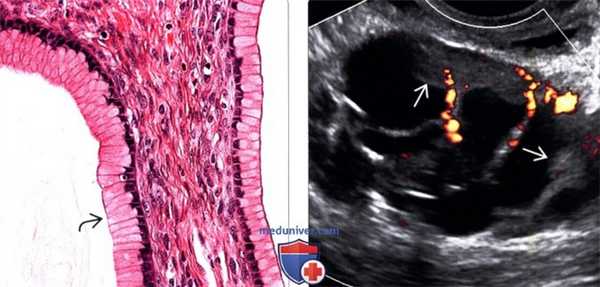

(Слева) Отмечается скопление свободной слизи в данной муцинозной цистаденоме, а в выстилающих опухоль клетках определяется богатая слизью цитоплазма.

(Справа) Солидные сосудистые компоненты, обнаруженные на трансвагинальной ультрасонографии, являются признаками муцинозной цистаденомы.

3. Микроскопические изменения:

• Кисты содержат вязкую жидкость

• Кисты выстланы однослойным муцинпродуцирующим эпителием без признаков атипии:

о Аналогичен эпителию цервикального канала или кишечника

• Строма яичника часто имеет высокую клеточность и содержит очаги лютеинизации

• Разрыв слизистых желез приводит к образованию гранулем, содержащих большое количество макрофагов

• Папиллярные выросты на стенке кист не характерны

• Стенки кист образованы фиброзной стромой